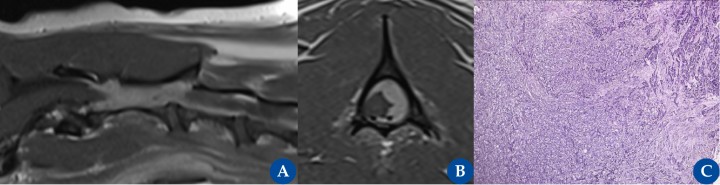

Meningioma espinal atípico canino (WHO grado II). Resonancia magnética: plano parasagital (A) y transversal T1 (B) post contraste en un perro, macho castrado, de 9 años de edad con una historia crónica progresiva compatible con una mielopatía cervical craneal (mielopatía C1-C5). Se observa una masa intradural-extramedular de gran tamaño que realza de manera homogénea tras la administración de contraste paramagnético (gadolinio), lateralizada hacia la izquierda desde el nivel del cuerpo craneal C2 al espacio del disco intervertebral C2-C3. La lesión provoca un efecto de masa sobre la médula, que se desplaza hacia el lado derecho, y está en contacto directo con la cara dorsal de la médula y con su superficie lateral izquierda. La imagen histopatológica [(C), imagen cedida por la Dr. Jéssica Molín] corresponde a la biopsia quirúrgica que muestra una proliferación neoplásica no encapsulada, de elevada densidad, compuesta por células atípicas, leve a moderadamente pleomórficas, predominantemente poligonales, organizadas en nidos sólidos de tamaño variable separados por finas trabéculas de tejido fibrovascular compatible con un meningioma atípico grado II.